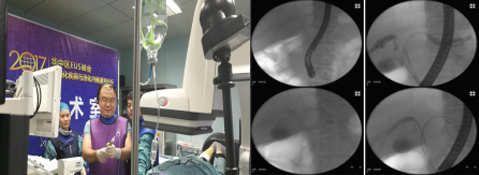

4月8日,由中华医学院消化内镜分会超声内镜学组主办的2017华中区EUS峰会暨消化疾病与消化内镜潇湘论坛在长沙举行。湘雅三医院肝胆胰外科邓刚副教授、徐宏博总住院医师、朱垒博士组成的手术团队受邀在大会演示高难度肝门部胆管癌双支架置入术,并与全国超声内镜学组组长金震东教授同台合作演示EUS引导下双蘑菇头支架胰腺假性囊肿引流术。

两例手术均获成功,反响热烈,充分体现湘雅三医院肝胆胰外科内镜微创技术影响力。

图为 肝门部胆管癌双支架置入解除胆道梗阻

图为我院团队与全国超声内镜学组组长金震东教授同台手术